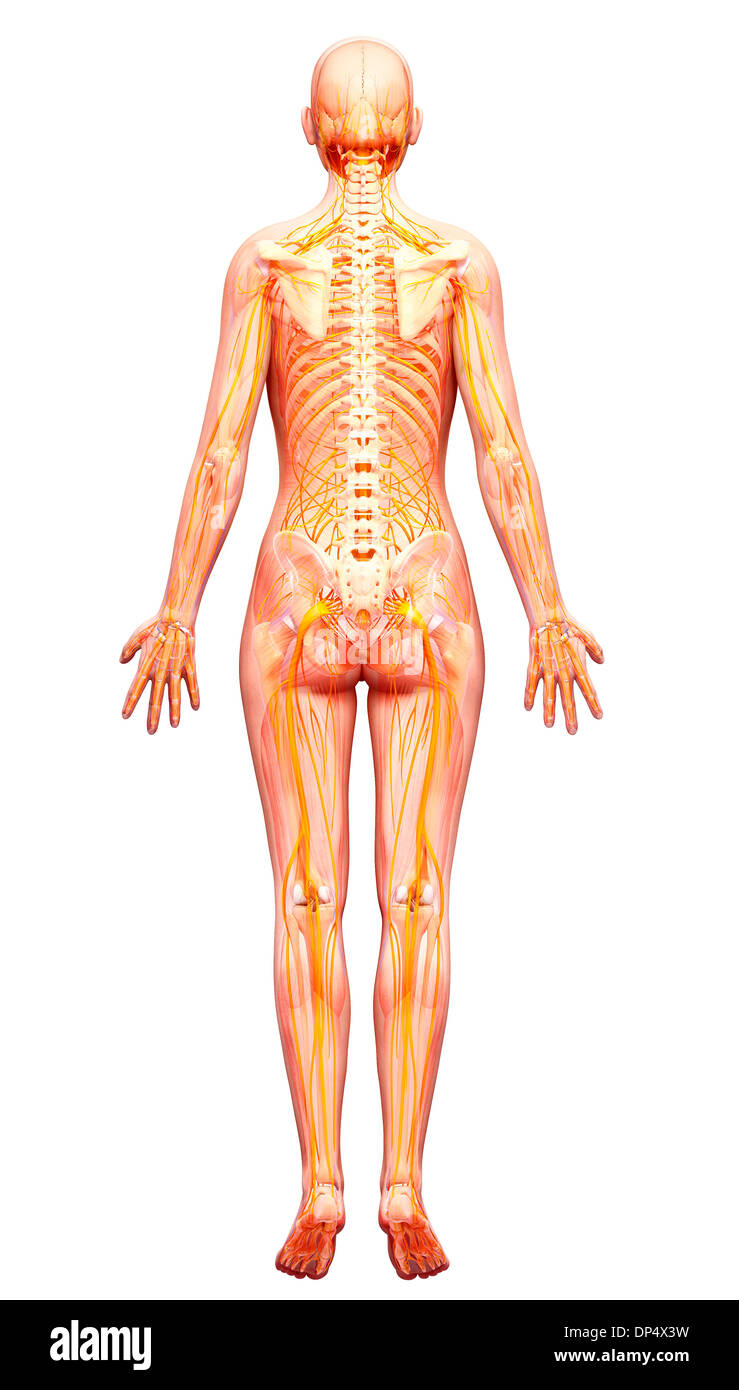

Système nerveux humain, artwork Banque D'Imageshttps://www.alamyimages.fr/image-license-details/?v=1https://www.alamyimages.fr/systeme-nerveux-humain-artwork-image65261837.html

Système nerveux humain, artwork Banque D'Imageshttps://www.alamyimages.fr/image-license-details/?v=1https://www.alamyimages.fr/systeme-nerveux-humain-artwork-image65261837.htmlRFDP4X3W–Système nerveux humain, artwork